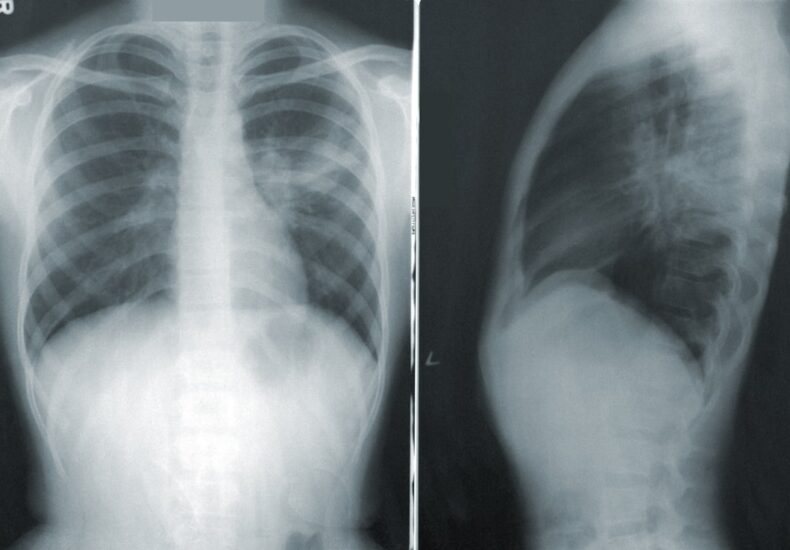

At their core, diagnostic imaging techniques such as X-rays, MRI scans, CT scans and ultrasounds provide visual representations of the interior of the body. These images allow healthcare professionals to see beneath the skin without invasive procedures, reducing patient risk and improving diagnostic accuracy. The ability to visualise bones, organs, tissues and other structures in detail has revolutionised medicine over the past century, leading to earlier diagnoses and better treatment outcomes.

The process of diagnostic imaging typically begins with a referral from a healthcare provider who suspects a condition that cannot be confirmed through physical examination alone. Depending on the symptoms and suspected issue, the patient may be scheduled for a specific type of scan. Each imaging modality has its own strengths. For example, X-rays are ideal for viewing bone fractures, while MRI scans are better suited for examining soft tissues like the brain or spinal cord. CT scans combine the benefits of X-rays and computer technology to create cross-sectional views of the body, making them highly effective in detecting tumours or internal bleeding.